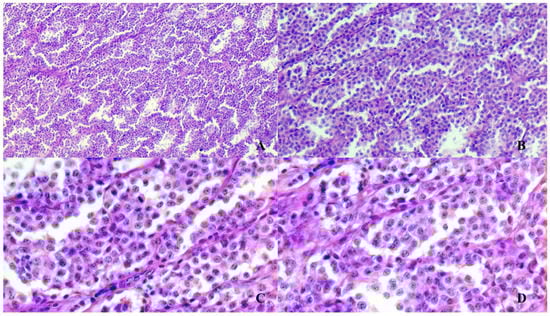

The histopathology investigations revealed a partially encapsulated infiltrative mass with multifocal angiotropic growth; the mass was composed of polygonal cells organized in nests, packs and bundles, all these structures being supported by a fine fibrovascular stroma (Figure 2). The lobules were lined peripherally by spindle cells. The tumor was highly vascular with blood-filled lacunae and multifocal to coalescing areas of liquefactive necrosis. The polygonal cells were characterized by indistinct borders, lightly eosinophilic cytoplasm with a moderate number of granules, round or oval central nuclei with stippled chromatin (“salt and pepper” appearance) and inconspicuous nucleoli. Anisocytosis and anisokaryosis were mild and mitoses were sporadic.

Figure 2.

Paraganglioma histopathological features. Typical structural pattern of paraganglioma organized in packs, nests and bundles of spindle cells supported by fibrovascular stroma. Hematoxylin-Eosin stain, magnification of 4× (A), 10× (B), 20× (C,D).